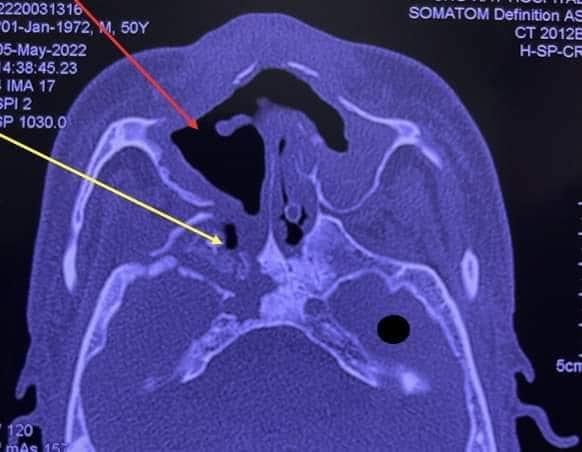

16 bệnh nhân này có đặc điểm chung là đều mắc COVID-19 trước đó, thời gian khởi phát từ 1 – 3 tháng sau mắc, đa số đều có bệnh nền là đái tháo đường. Triệu chứng thường gặp nhất là lung lay răng và xương hàm trên (cả khối), có lỗ rò mủ, sưng đau vùng khẩu cái (vòm miệng), có những vết loét và lộ xương hàm trên. Kết quả chẩn đoán hình ảnh giúp thấy rõ mức độ lan rộng của xương hoại tử.